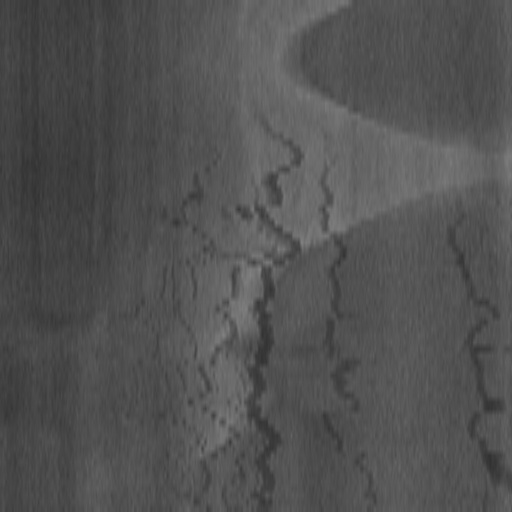

A.2 Temporal Coherency

Our method takes an entire X-ray video as input, thus producing segmentation results with better temporal coherency. Temporal coherency is essential for making medical diagnoses, especially when dealing with blood flow in vessels. Therefore, we conduct visual comparisons between our method and other compared methods by slicing horizontally or vertically and stacking the segmentation results. The results in Figure 11 show our method strikes a better balance between segmentation accuracy and temporal coherency. While other baseline methods either produce false segmentation results or do not maintain consistent prediction along the temporal dimension.